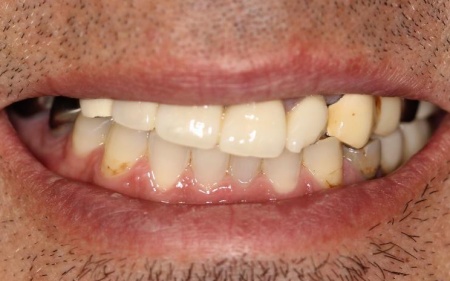

「30代から歯科医院に通っていたが、歯が痛むときだけしか受診しなかったせいか、歯が折れて欠損部が増え、噛みにくくなってしまった。また、今までいくつかの歯科医院を受診したが解決が難しく、こちらを受診した」とご相談いただきました。

拝見したところ、右上奥歯4本が欠損しており、その影響で全体の噛み合わせのバランスが崩れていました。

加えて、噛んだときに上下の歯の中心がずれており、顔貌のゆがみにもつながっています。

欠損部が多い状態が長期間続いたことで噛み合わせが低く、新しい歯を入れるための高さも不足していました。

また、右上前歯も1本欠損しており、両隣の歯を土台として橋を渡すように連結した被せ物「ブリッジ」が装着されていましたが、土台となっている右上前歯2本(中切歯、犬歯)が割れており、温存が難しい状態です。

さらに、劣化してうまく適合していない被せ物、詰め物、既存のインプラントが複数見られ、これらも噛み合わせを乱す原因となっていました。

加えて全体的に歯周病も進行しており、骨が溶けている部分も確認できます。

このまま放置すると、食事がしにくい、残っている歯への負担が増えて歯の寿命が短くなるなどのリスクがあるため、早急に治療を開始する必要があると診断しました。